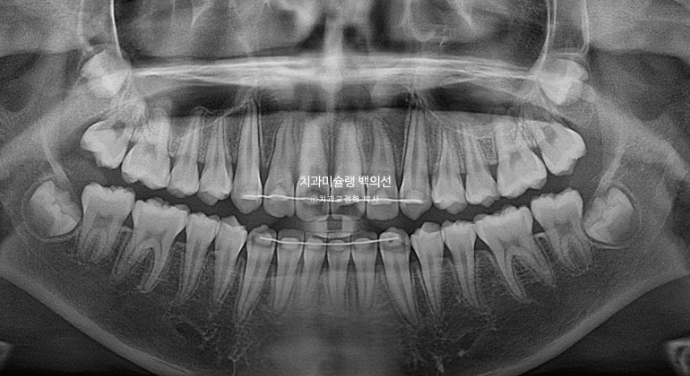

앞니 치축의 개선은 엑스레이에서 더 정확히 확인이 됩니다.

24.02~25.07